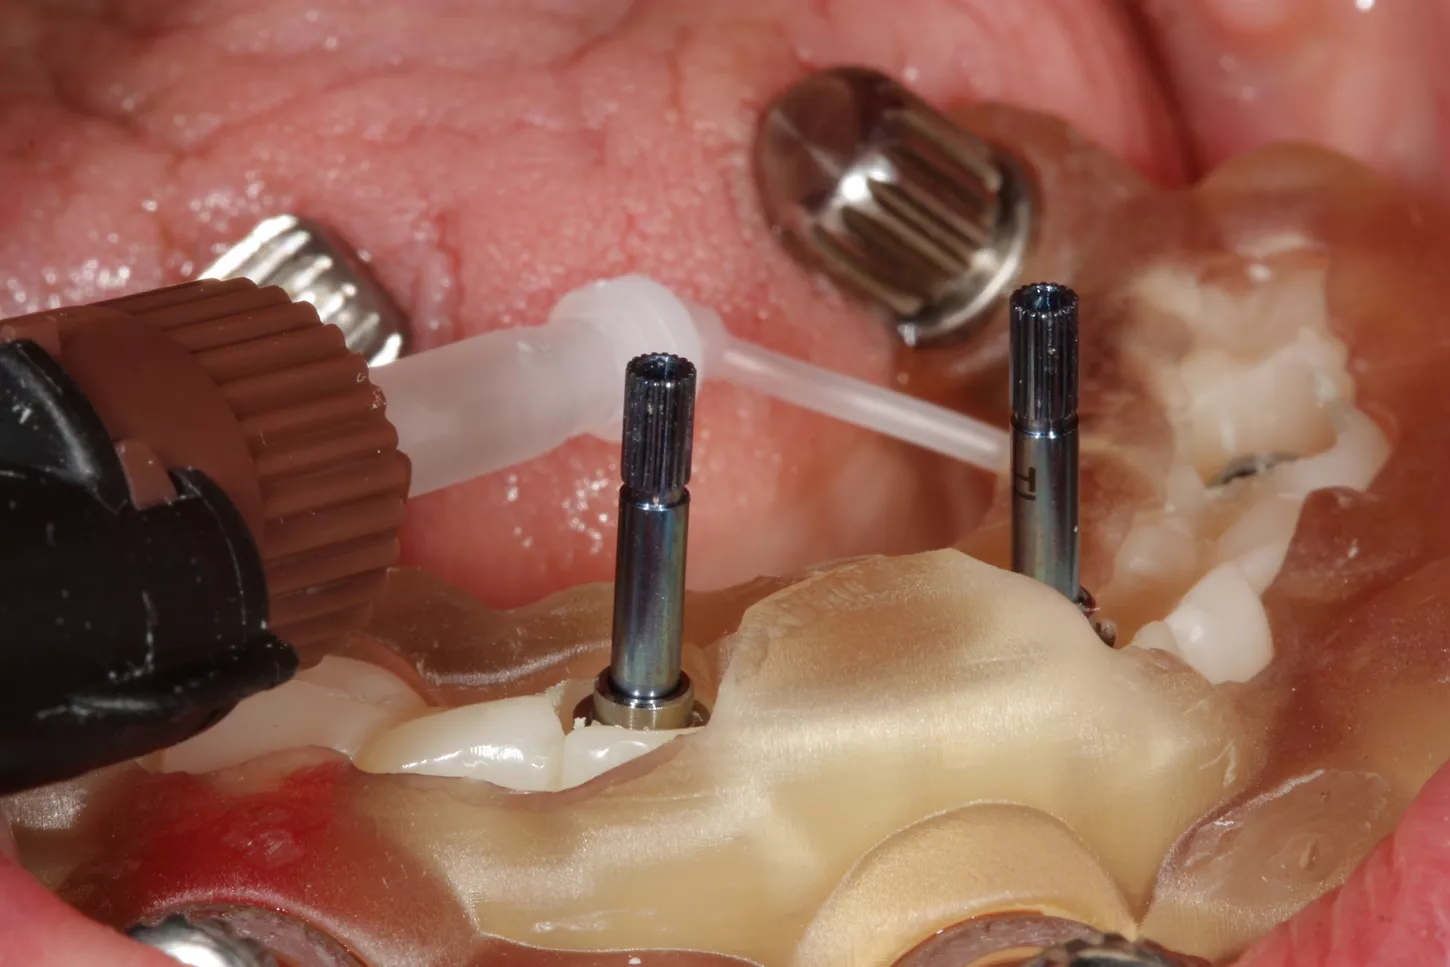

9.  Positioning of the Tissue Level temporary abutments platform N plural reference number TC100-N-P to accommodate the prefabricated temporary restoration.

10.  The temporary restoration is positioned in the mouth using the final stackable splint to ensure that the patient's original occlusion is maintained. The temporary restoration is bonded intraorally around the temporary abutments. Despite the precise implant positioning, there may be slight deviations in the dental arch, so this procedure is recommended.